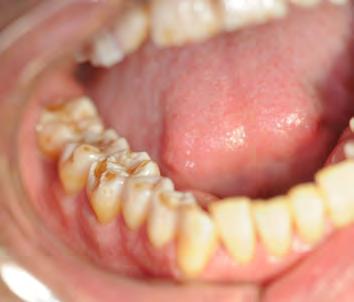

Figure 3. Frequency of hypertension medications by specific classes.

Antihypertensives were the most common therapeutic class of medications among our subjects, at 49.4% (n = 80). As seen in Fig ures 2 and 3, when hypertension medications (color-coded green) are further subdivided into pharmacologic classes, beta blockers were the most associated with OLL/OLP, followed closely by angiotensinII-receptor blockers (ARBs) and calcium channel blockers (CCB). The thiazides are the next frequent type of hypertension medications taken by our OLL/OLP patient cohort. To our knowledge, our study is the first to further subtype the large and diverse class of hyperten sion medications associated with oral lichenoid lesions.